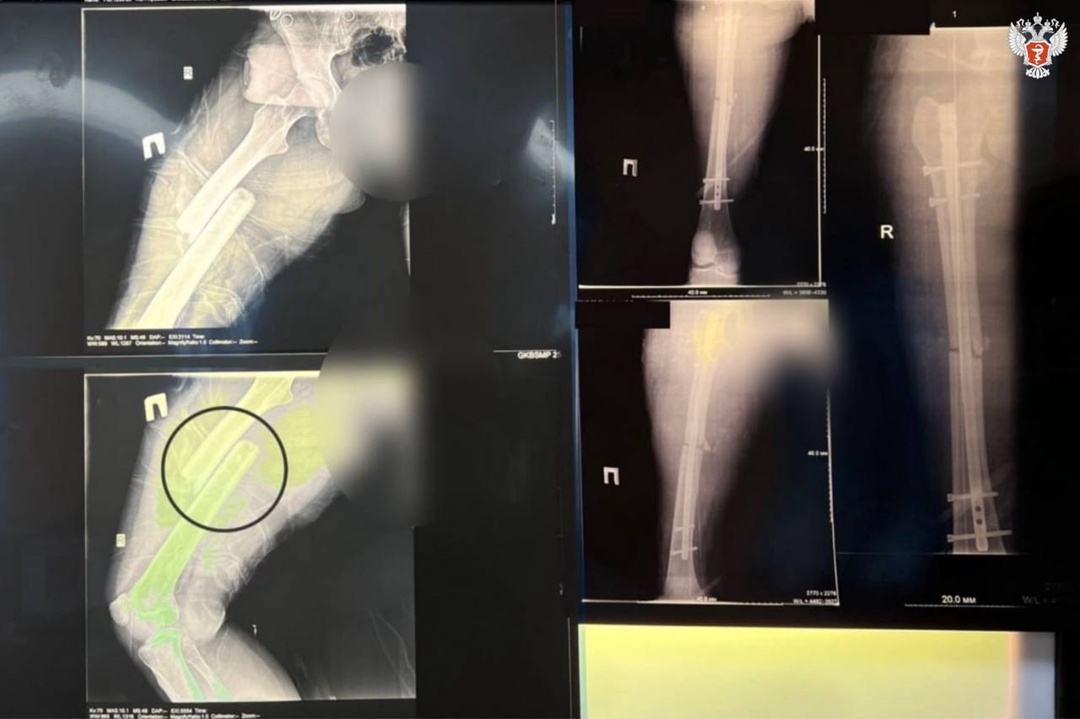

➡️ Специалисты диагностировали у пациентки закрытую черепно-мозговая травму, открытый перелом бедренной кости со смещением и перелом вертлужной впадины (тазовых костей).

— Поскольку при поступлении захождение отломков бедренной кости друг за друга составляло более 11 см, была настроена система скелетного вытяжения. На рентген-контроле через несколько дней мы выявили, что захождение практически устранено в следствие поэтапного добавления груза на скелетное вытяжение, —

После заживления ран бедра пациентке провели остеосинтез бедренной кости.

Такая операция проводится с минимальной кровопотерей благодаря малоинвазивной методике: врачи через микроразрезы ввели штифт в кость и зафиксировали его винтами.